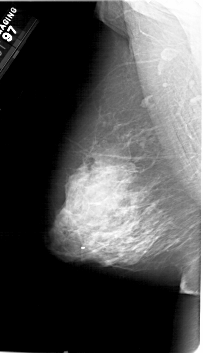

A_1218_1.LEFT_MLO

LEFT_MLO LINES 6706 PIXELS_PER_LINE 3841 BITS_PER_PIXEL 12 RESOLUTION 43.5 NON_OVERLAY